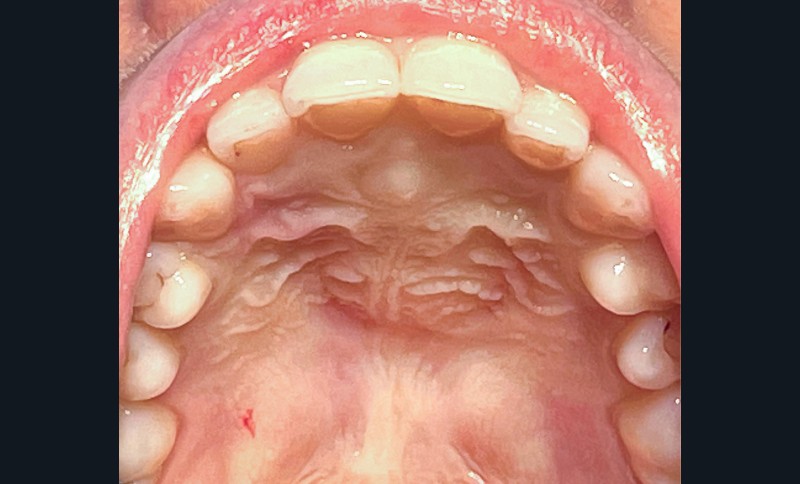

- Les symptômes, lorsqu’ils existent, sont le plus souvent en rapport avec une tuméfaction palatine rétro-incisive (fig. 2) ou des douleurs amenant le patient à consulter.